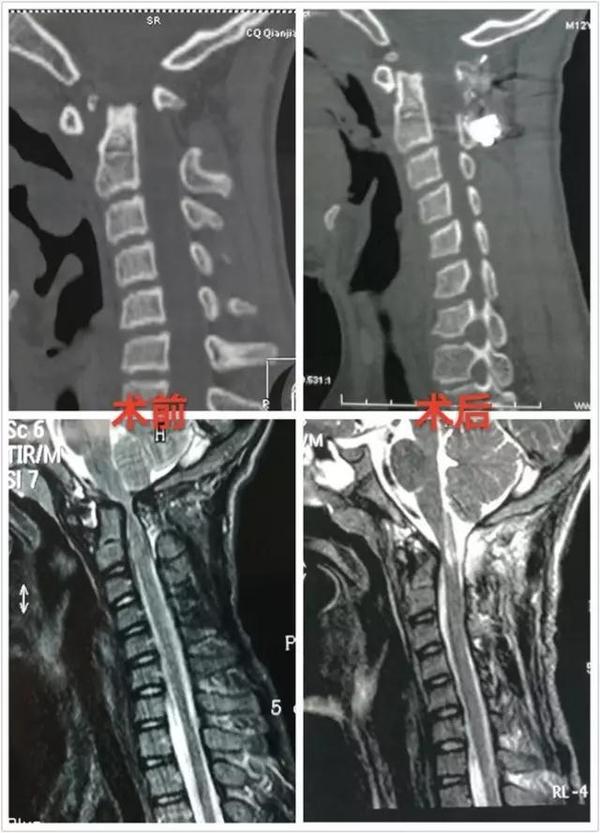

术前术后对比

1、本例寰椎发育良好,没有寰枕融合,故选择C1-2复位+固定融合。

2、术后复查见复位满意,脊髓减压充分,颈脊角纠正满意。

3、分析术前影像,本例为先天性颅颈畸形,外伤是导致其病情加重的诱因。理由:齿状突小骨和颈2椎体有皮质骨面;颈2变异,为先天性畸形证。

4、采用Goel技术治疗寰枢椎脱位,短节段固定融合,枕颈活动丢失较小,术后发生断钉断棒风险小,在一定程度上优于枕颈融合复位固定手术。